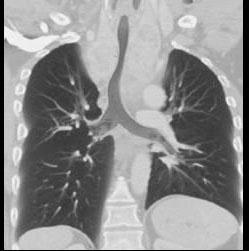

男,67岁,呼吸困难半年余,请结合影像学检查,选出最可能的诊断 ( )A、纵隔畸胎瘤B、胸腺瘤C、淋巴瘤D、间皮囊肿E、胸骨后甲状腺肿

问题 男,67岁,呼吸困难半年余,请结合影像学检查,选出最可能的诊断 ( )

选项 A、纵隔畸胎瘤 B、胸腺瘤 C、淋巴瘤 D、间皮囊肿 E、胸骨后甲状腺肿

答案 E